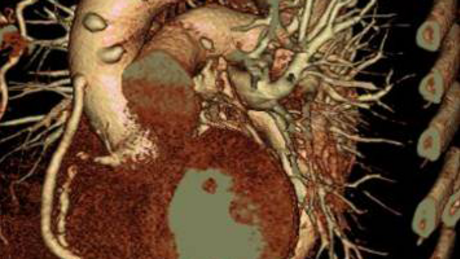

Bild 1: Dreidimensionale Darstellung des Herzens, die Herzkranzgefäße kommen unauffällig zur Darstellung

Bild 3: Dreidimensionale Darstellung des Herzens, der Hauptschlagader (Aorta) und von einem offenen und zwei verschlossenen Bypassgefäßen.